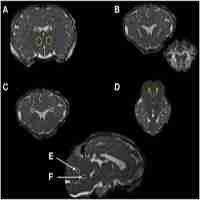

| Abstract | BACKGROUND AND AIM: High tidal volume (VT) ventilation during resuscitation of preterm lambs results in brain injury evident histologically within hours after birth. We aimed to investigate whether magnetic resonance spectroscopy (MRS) and/or diffusion tensor imaging (DTI) can be used for early in vivo detection of ventilation-induced brain injury in preterm lambs. METHODS: Newborn lambs (0.85 gestation) were stabilized with a "protective ventilation" strategy (PROT, n = 7: prophylactic Curosurf, sustained inflation, VT 7 mL/kg, positive end expiratory pressure (PEEP) 5 cmH2O) or an initial 15 minutes of "injurious ventilation" (INJ, n = 10: VT 12 mL/kg, no PEEP, late Curosurf) followed by PROT ventilation for the remainder of the experiment. At 1 hour, lambs underwent structural magnetic resonance imaging (Siemens, 3 Tesla). For measures of mean/axial/radial diffusivity (MD, AD, RD) and fractional anisotropy (FA), 30 direction DTI was performed. Regions of interests encompassed the thalamus, internal capsule, periventricular white matter and the cerebellar vermis. MRS was performed using a localized single-voxel (15×15×20 mm3, echo time 270 ms) encompassing suptratentorial deep nuclear grey matter and central white matter. Peak-area ratios for lactate (Lac) relative to N-acetylaspartate (NAA), choline (Cho) and creatine (Cr) were calculated. Groups were compared using 2-way RM-ANOVA, Mann-Whitney U-test and Spearman's correlations. RESULTS: No cerebral injury was seen on structural MR images. Lambs in the INJ group had higher mean FA and lower mean RD in the thalamus compared to PROT lambs, but not in the other regions of interest. Peak-area lactate ratios >1.0 was only seen in INJ lambs. A trend of higher mean peak-area ratios for Lac/Cr and Lac/Cho was seen, which correlated with lower pH in both groups. CONCLUSION: Acute changes in brain diffusion measures and metabolite peak-area ratios were observed after injurious ventilation. Early MRS/DTI is able to detect the initiation of ventilation-induced brain injury. |